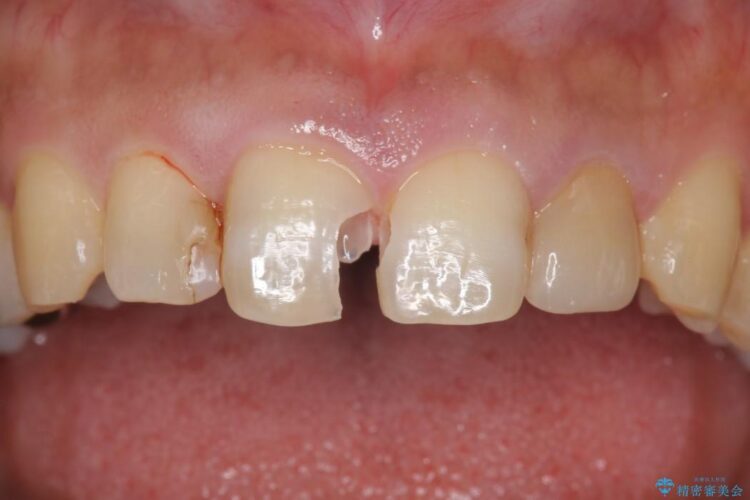

虫歯による歯の欠けと変色を主訴に来院されました。

神経に届く一歩手前の虫歯を前歯に認めました。

虫歯の範囲が大きいため詰め物ではなく、被せ物を使用した治療を行うこととしました。